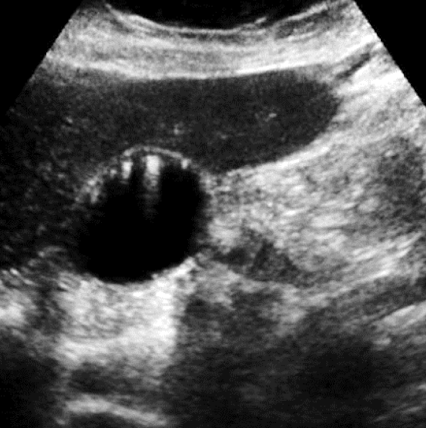

adenomyomatosis

cholesterol crystals that settle within the Rokitansky-Aschoff sinuses of GB wall

mucosal hyperplasia (thickening of muscular layer of GB wall); papillomas occur

SONO: thickening of wall with internal cystic spaces

echogenic foci on wall with “comet tail” artifact

??